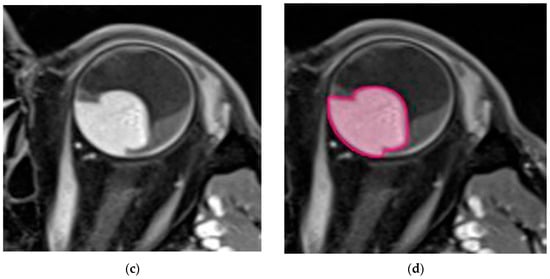

Three-dimensional beam arrangements were set and premeditated for each case, to deliver highly conformal prescription dose distributions. Four or more non-opposing, non-coplanar beams were selected. Entry and exit fields were individually optimized, and were required not to pass through the skull base, brain or body trunk below the upper borders of the breasts. The field aperture dimension corresponded to the beam’s eye view (BEV) projection of the PTV. The field arrangements (entrance–exit fields) were set up so as not to pass through sensitive structures. The main couch angles, as well as the gantry starting and stopping angles, were set up beneath the skull base, in accordance with the other OARs, to complete the trajectory optimization. A representative beam arrangement is shown in Figure 3a,b.

Figure 3.

(a) Stereotactic radiosurgery (SRS) by image-guided (IG) volumetric modulated arc therapy (VMAT) for patients with unfavorable-risk, large intraocular melanoma: representative 3D beam arrangements—axial plane. (b) Stereotactic radiosurgery (SRS) by image-guided (IG) volumetric modulated arc therapy (VMAT) for patients with unfavorable-risk, large intraocular melanoma: representative 3D beam arrangements—sagittal plane.